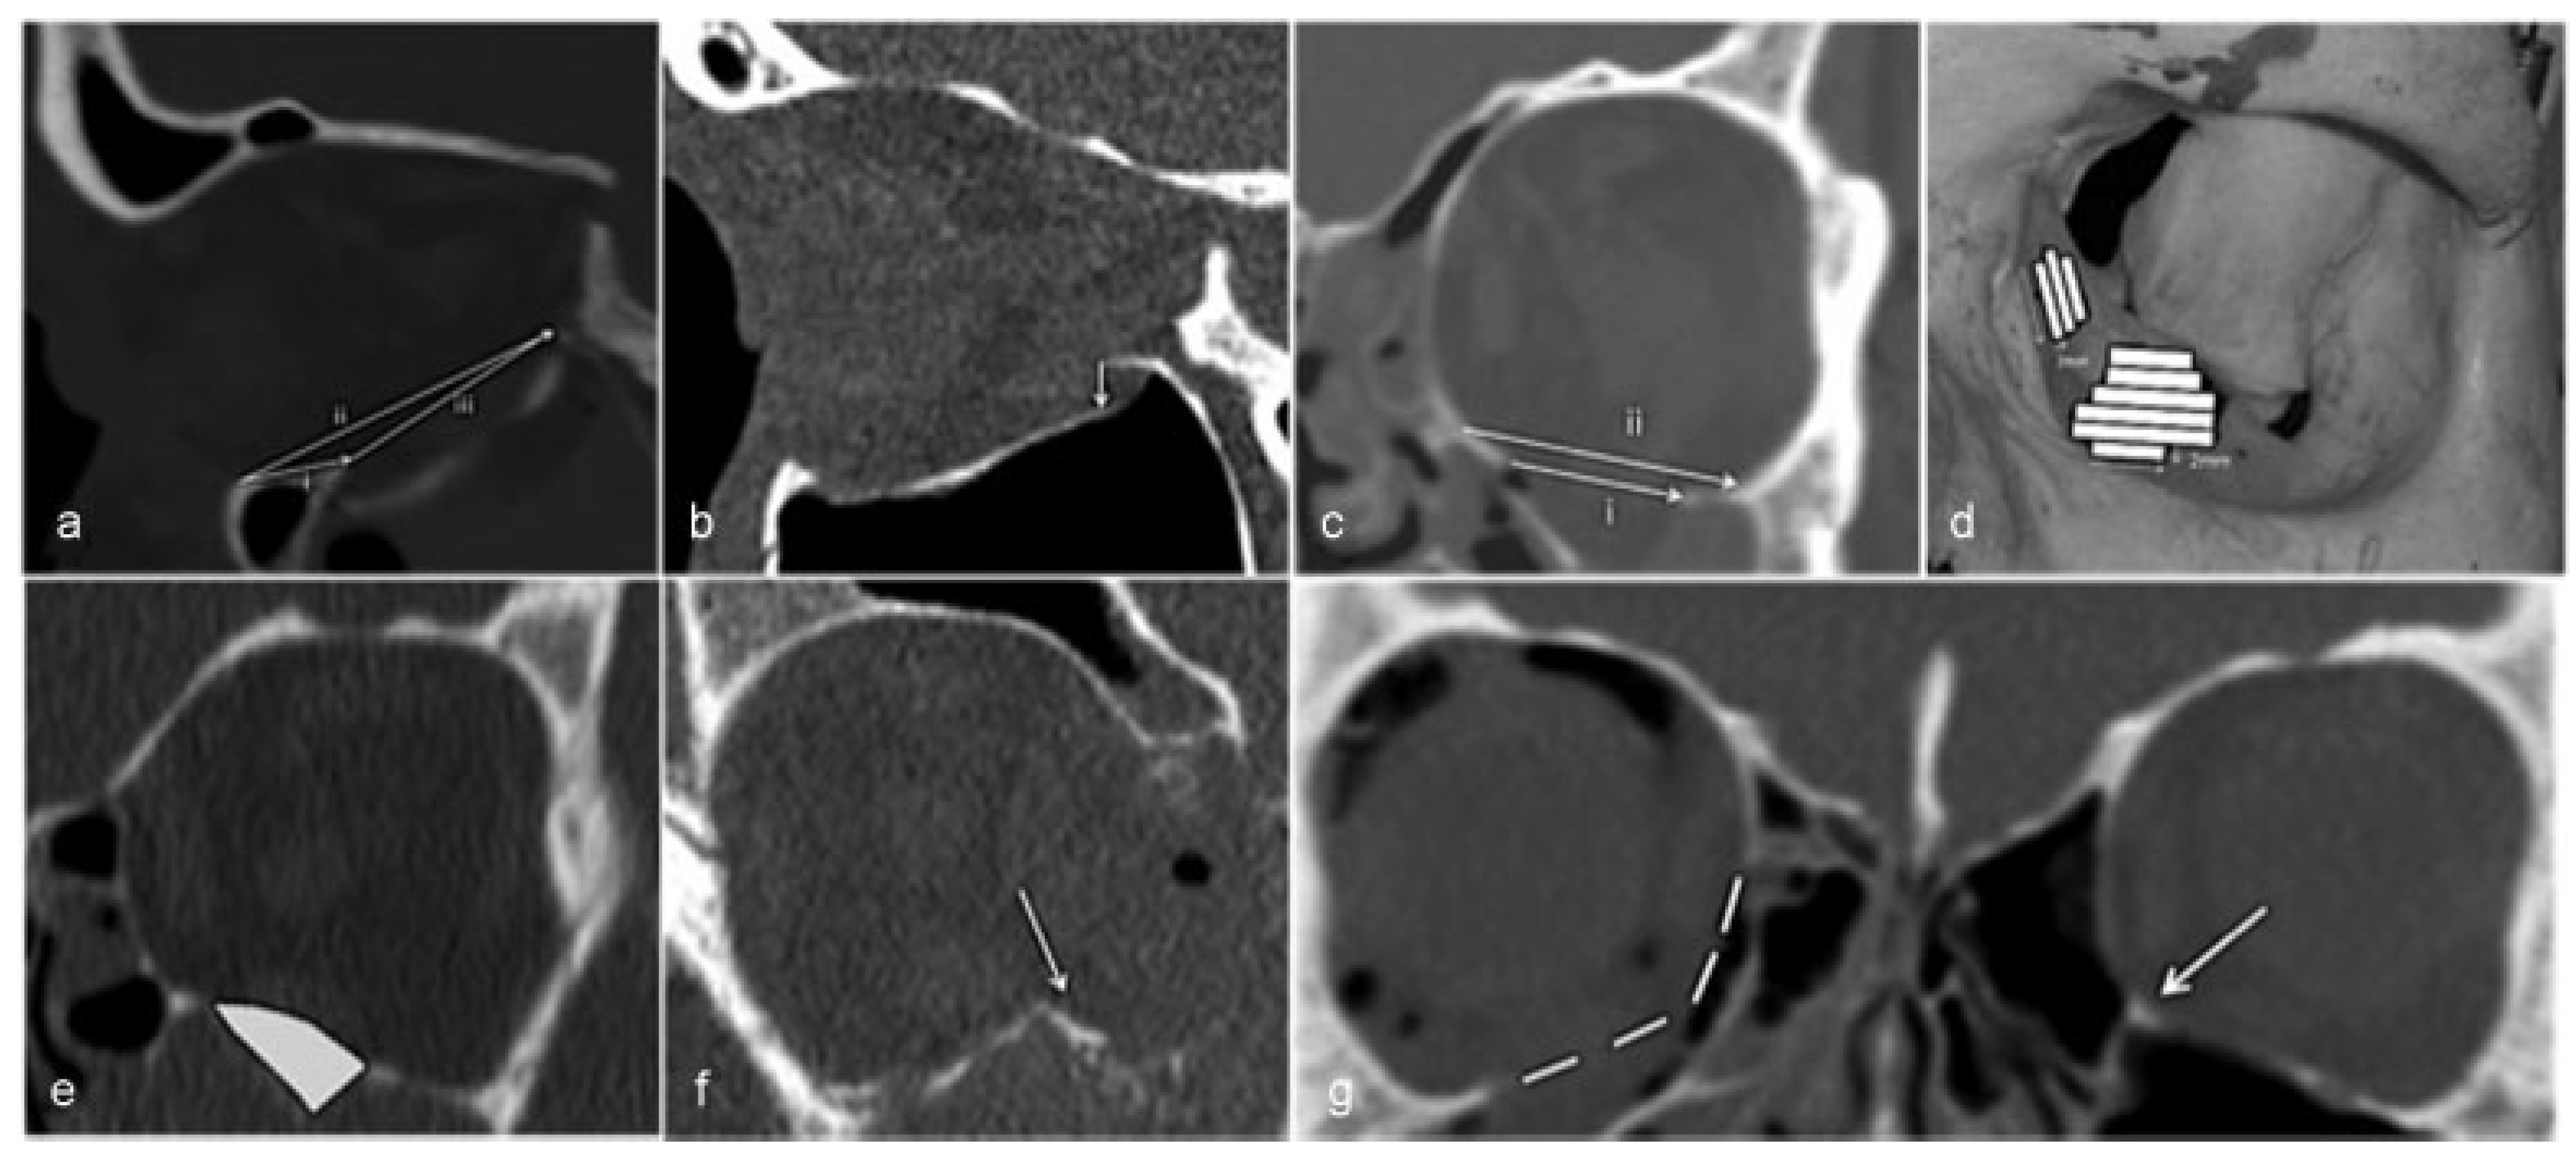

The CT scans were performed with ≤2-mm slices. All CT scans of patients who completed the study were analyzed for several measurements, see Table 1. They were transferred to a workstation (GE Healthcare Advantage Workstation version 4), where the images were evaluated in axial, coronal, and sagittal planes in an osseous window level setting according to a previous study [17]. The method we used in all the measurements of the CT scans (Figure 1) is described and used again in our other study [18].

Measurements were made accordingly: Sagittal plane where the fracture was considered largest in the inferior wall:

- The distance from the inferior orbital rim to the anterior edge of the fracture (Figure 1a, i), on the same slice.

- The distance from the inferior orbital rim to the posterior edge of the fracture (Figure 1a, ii), on the same slice.

- The longest anteroposterior length of the fracture (Figure 1a, iii).

- The degree of displacement of orbital bulge in mm (Figure 1b).

Coronal plane:

Figure 1.

(a) Inferior orbital rim to anterior edge of the fx i, posterior edge of the fx ii, and the longest anteroposterior length of the fx iii. (b) Displacement of orbital bulge. (c) Largest width of the fx i and the orbital floor ii. (d) Area of the fx. (e) Volume of the herniated orbital tissue. (f) Medial buttress fractured and dislocated. (g) Estimation of displaced inferomedial buttress in comparison with the unfractured contralateral orbit and inferomedial buttress (arrow).

Area

We performed a quantitative computational method for calculating the area of the fractures [19,20]. Stacks of 2-mm slices in the coronal plane were created. The width of the fractured orbital wall in each 2-mm slice was measured. This resulted in trapezoidal strips with a known area (see Figure 1d). The areas of the strips were combined to calculate the entire area of the fracture. Where the inferomedial buttress was displaced, the measurement was estimated after comparison with the unfractured contralateral orbit (Figure 1g).

Volume

The CT scans used were axial raw thin slices in a soft-tissue window setting (HU 600/1000) to distinguish blood from orbital fat and muscle tissue. The following steps were taken: “VR tools”; “Segment”; and “Quick paint” with brush size of 2 mm. The herniated content was marked green in one slice and then scrolled two to three steps posteriorly to mark the content again. This was repeated until all the content was marked in this plane. Then the same procedure was performed in the sagittal plane to fill in the gaps between the coronal slices. In the medial fractures, the coronal and axial planes were used instead. The marked area was applied and the “display tools” were used. The “Threshold” was set between −300 and 200 to exclude bone and air. To measure volume, the “Globe” function was used.